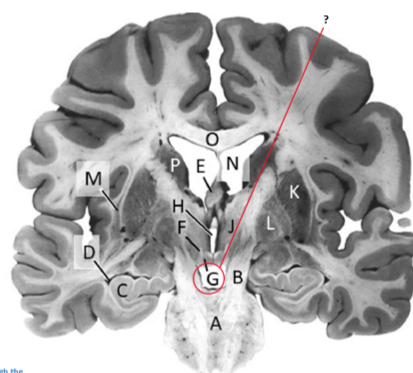

Name this and state its function.

Corpus Callosum.

Name and state its function.

Lateral ventricles.

Hippocampus.

Thalamus.

Third ventricle.

Caudate nucleus.

Name this ,state its function and the name of the structures closely associated with it.

Putamen.

Name this, state its function and its components[4 marks].

Globus Pallidus.

Crus Cerebri.

Name this and state its function. Also, state all 3 fibres involved.

Basilar pons.

Claustrum.

Name.

Temporal horn of lateral ventricle.

Name this, state its function and consequence of lesion in this area.

Fornix.

Lesion: anterograde amnesia.

Name this and state its function. And what tract is involved?

Mamillary bodies.